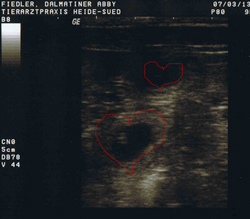

Heute, am 07.03. waren wir beim Ultraschall, und können berichten... Abby ist tragend, juchu!!!

Hier sieht man schon die kleinen Früchte, die bald zu zu kleinen Dalmatinern heranwachsen.